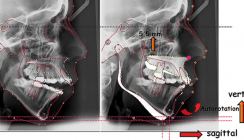

Das OPG (Abb. 3) zeigt, dass alle Zähne einschließlich alle 8er vorhanden sind, die vor der Operation entfernt wurden, weil sie im Operationsfeld standen. Die FRS-Aufnahme zeigt deutlich die Dysgnathie in der Sagittalen und Vertikalen sowohl im Weichteilprofil als auch im skelettalen Bereich: mesiobasale Kieferrelation und strukturell neutrales abgelaufenes Wachstumsmuster. Die vertikale Einteilung des Weichteilprofils zeigte eine Disharmonie zwischen dem Ober- und Untergesicht (G’-Sn : Sn-Me’; 45 % : 55 %). Diese äußerte sich ebenso in den knöchernen Strukturen (N-Sna : Sna-Me; 41 % : 59 %). Im Bereich des Untergesichtes bestand eine harmonische Relation (Sn-Stms : Stms-Me’; 33 % : 67 %) (Abb. 4, Tab. 1). Die dentale Analyse zeigt eine dentoalveolare Kompensation der skelettalen Dysgnathie; nahezu achsengerecht stehende Oberkieferfront, während die Unterkieferfront nach lingual gekippt steht (Tab. 1).

Die Verbesserung der Gesichtsästhetik in der Vertikalen sollte durch eine relative Verkürzung des Untergesichtes erfolgen. Eine Verkürzung des Untergesichtes als kausale Therapie mit entsprechendem Effekt auf die faziale Ästhetik und Lippenfunktion konnte bei dieser Patientin nur durch eine kombiniert kieferorthopädisch-kieferchirurgische Behandlung erreicht werden. Mit alleinigen orthodontischen Maßnahmen wären die angestrebten Ziele hinsichtlich der Ästhetik und Funktion nicht zu erreichen gewesen. Als Operation wurde eine bimaxilläre Osteotomie geplant. Zur Verbesserung der Vertikalen war eine Oberkieferimpaktion notwendig, die im dorsalen Bereich stärker als im ventralen Bereich durchgeführt werden sollte.22,23 Als Folge der Impaktion sollte der Unterkiefer mit den Kondylen als „Rotationszentrum“ in der Sagittalen und Vertikalen autorotieren; dabei war eine Verlagerung des Pogonion nach ventral und gleichzeitig nach kranial zu erwarten (Abb. 5). Zur vollständigen Korrektur der sagittalen Dysgnathie war zusätzlich eine Unterkieferrückverlagerung geplant.